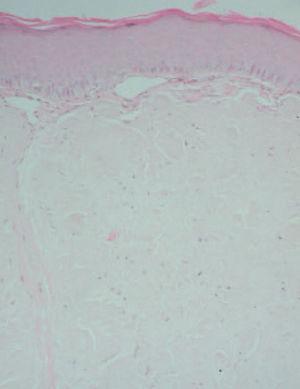

En la exploración, se observó un tumor de 2 cm de diámetro, de bordes bien definidos, en línea media del dorso lingual, de coloración amarillenta y superficie lisa y brillante (fig. 1). Estaba ligeramente infiltrado a la palpación, y no se objetivaba macroglosia ni otras lesiones de interés en el interior de la cavidad oral. El resto de la exploración física se encontraba dentro de la normalidad. Se realizó una biopsia de la lesión que reveló una importante presencia de material amiloide en toda la submucosa como pudo demostrarse mediante tinciones de rojo Congo y tioflavina T (figs. 2 y 3). Asimismo se realizó una tinción para cadenas ligeras que resultó negativa. Con el diagnóstico de amiloidosis cutánea se realizaron pruebas complementarias, entre las que se incluyeron hemograma y bioquímica completos, radiografía de tórax, ecografía abdominal, ecocardiograma, médula ósea, determinación de anticuerpos antinucleares (ANA), 2-microglobulina, factor reumatoide y proteinograma, así como una biopsia de mucosa rectal. Todas estas pruebas se encontraban dentro del rango de la normalidad, y tan sólo se halló una insuficiencia mitral ligera en el ecocardiograma.

Fig. 3.—Fluorescencia de los depósitos con tioflavina T (×100).